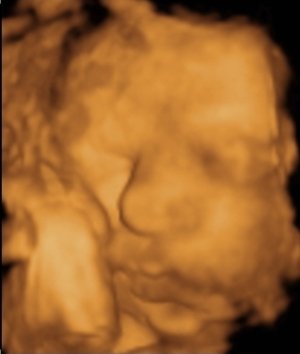

Alex baba nagyon édes!